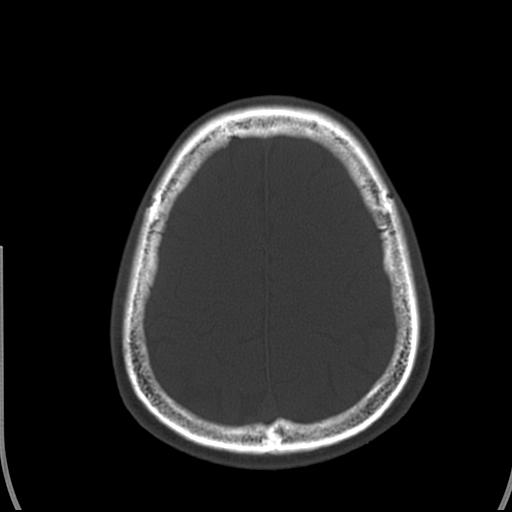

标题: CT25435:头皮下高密度影???

头皮下高密度结节影???临床上在老年男性比较常见。大家看看是什么?成因是? 本例患者,男性,51岁。外伤来诊。无染发史及发根植入史。

皮下钙化点

没见过,可能为毛囊钙化。

考虑钙化。